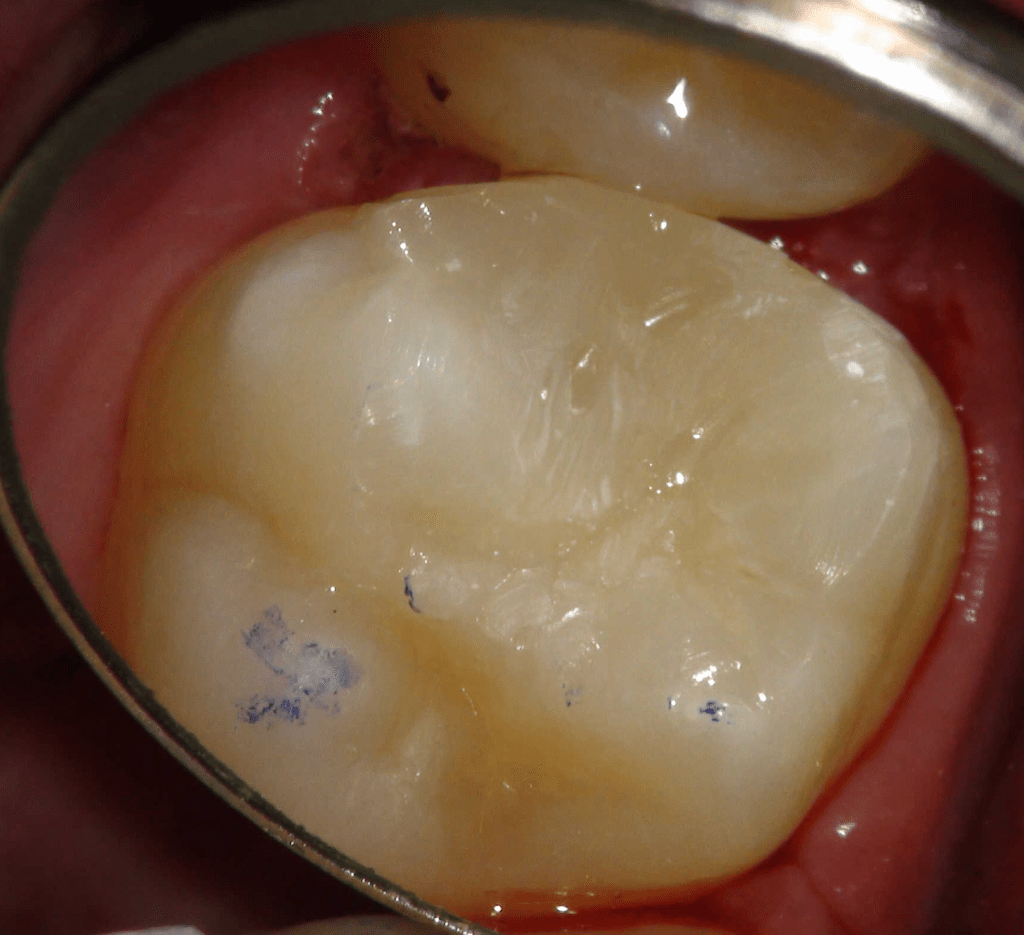

Pulpotomía biodentine + reco preendio